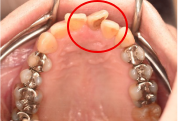

女性Mさん 50代(オールセラミック冠)

主訴

上の前歯をきれいにしたい。

治療内容

前歯3本にオールセラミック冠を被せて、歯並び及びすり減った歯を審美的に回復しました。歯ぎしりが強くあることがわかりましたので、マウスピースを使ってもらう事にしました。

所感

一番オススメな方法は、矯正をし、歯並びを整えた後、すり減って形が変わってしまった歯に被せ物をすることをお話ししました。患者さんは、3本に被せ物をすることにより歯並びをきれいにすることを希望されました。

治療後、「曲った前歯が長年コンプレックスでした。セラミックの歯の色合いや形が自然な仕上がりで、相談して本当に良かったです!神経を抜くこともなく治療ができ、予定よりも低料金にしてもらえたのがありがたかった。先生も、歯科衛生士さんも事務の人も皆、優しく寄り添った対応をしてくれました。ありがとうございました!」と、とても嬉しいお話しをしてくださいました。

オールセラミック冠3本:¥93,500(生活歯)×3本=¥280,500(税込)